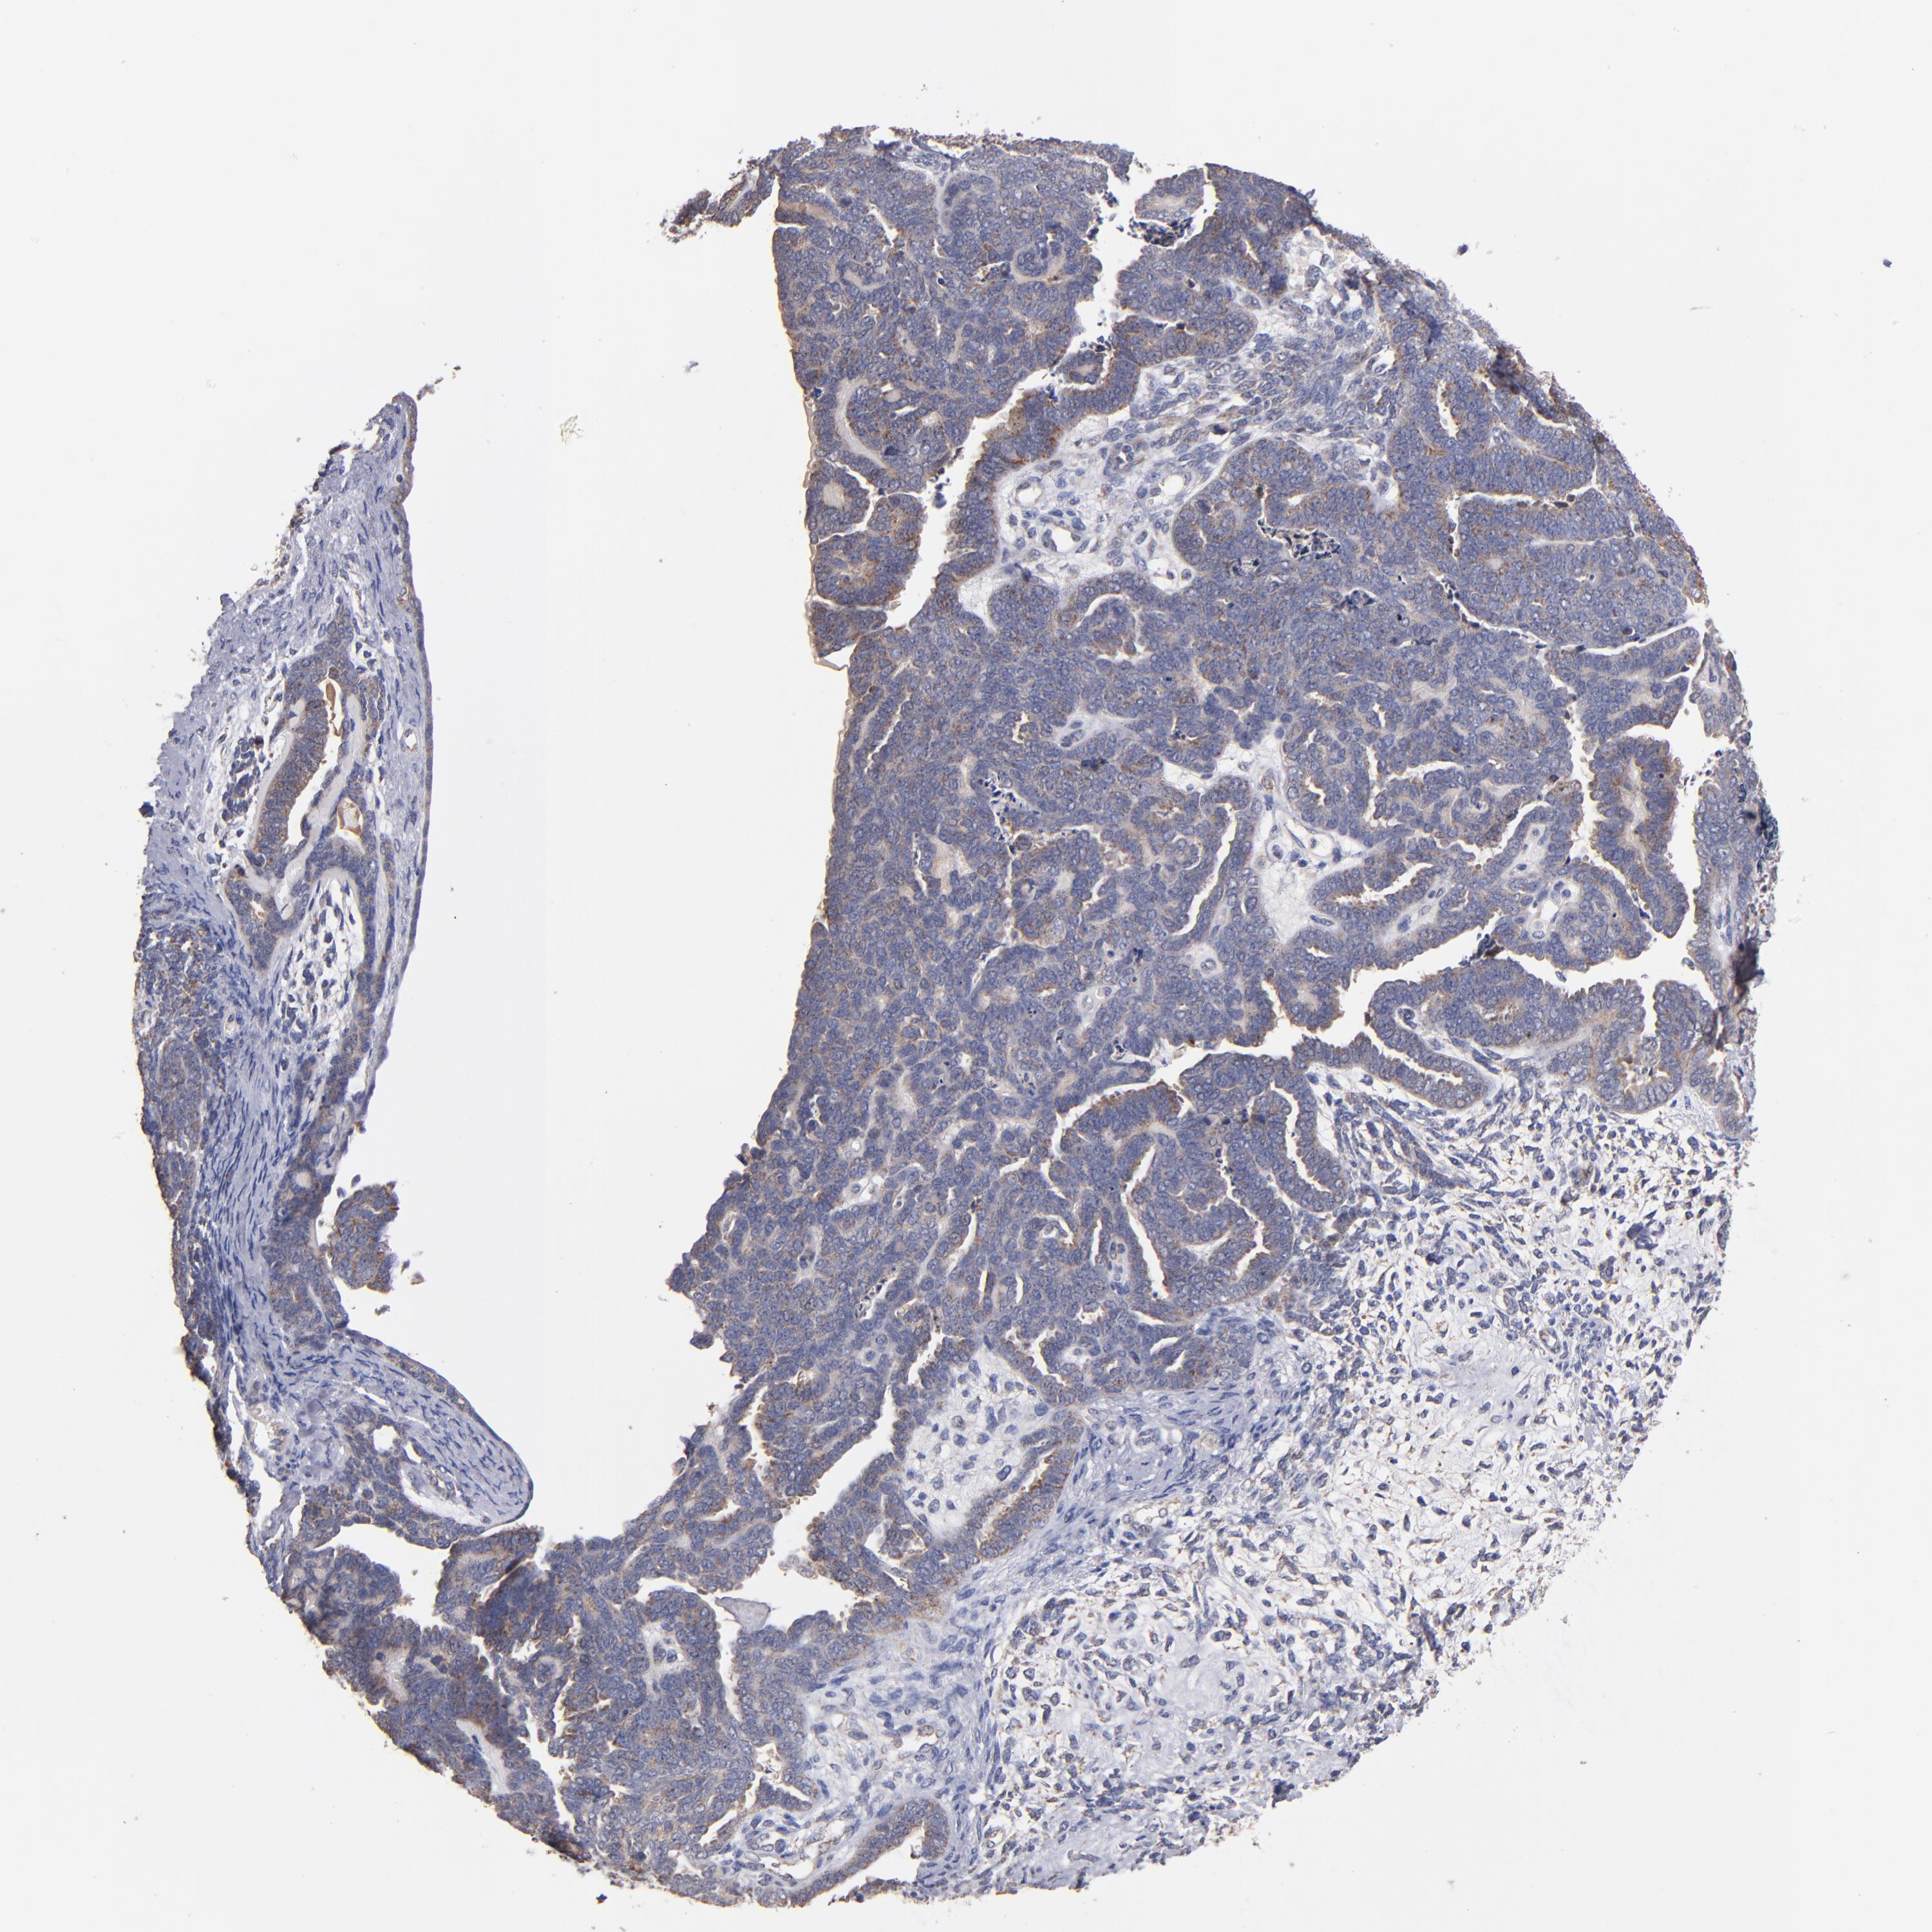

ENDOMETRIAL CANCER - Protein expressioni

A mouse-over function shows sample information and annotation data. Click on an image to view it in a full screen mode. Samples can be filtered based on level of antibody staining by selecting one or several of the following categories: high, medium, low and not detected. The assay and annotation is described here.

Note that samples used for immunohistochemistry by the Human Protein Atlas do not correspond to samples in the TCGA dataset.

Antibody stainingi

Antibody staining in the annotated cell types in the current human tissue is reported as not detected, low, medium, or high, based on conventional immunohistochemistry profiling in selected tissues. This score is based on the combination of the staining intensity and fraction of stained cells.

Each image is clickable and will lead to virtual microscopy that enables deeper exploration of all samples and also displays staining intensity scores, fraction scores and subcellular localization as well as patient and tissue information for each sample.

Antibody HPA001825

Antibody CAB003857

Staining

High

Medium

Low

Not detected

Intensity

Strong

Moderate

Weak

Negative

Quantity

>75%

75%-25%

<25%

None

Location

Nuclear

Cytoplasmic/membranous

Cytoplasmic/membranous,nuclear

Adenocarcinoma, NOS

Neoplasm, malignant, NOS